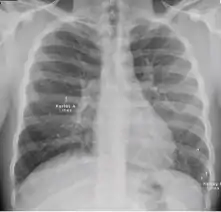

Chest x-ray of Ghon's complex of active tuberculosis